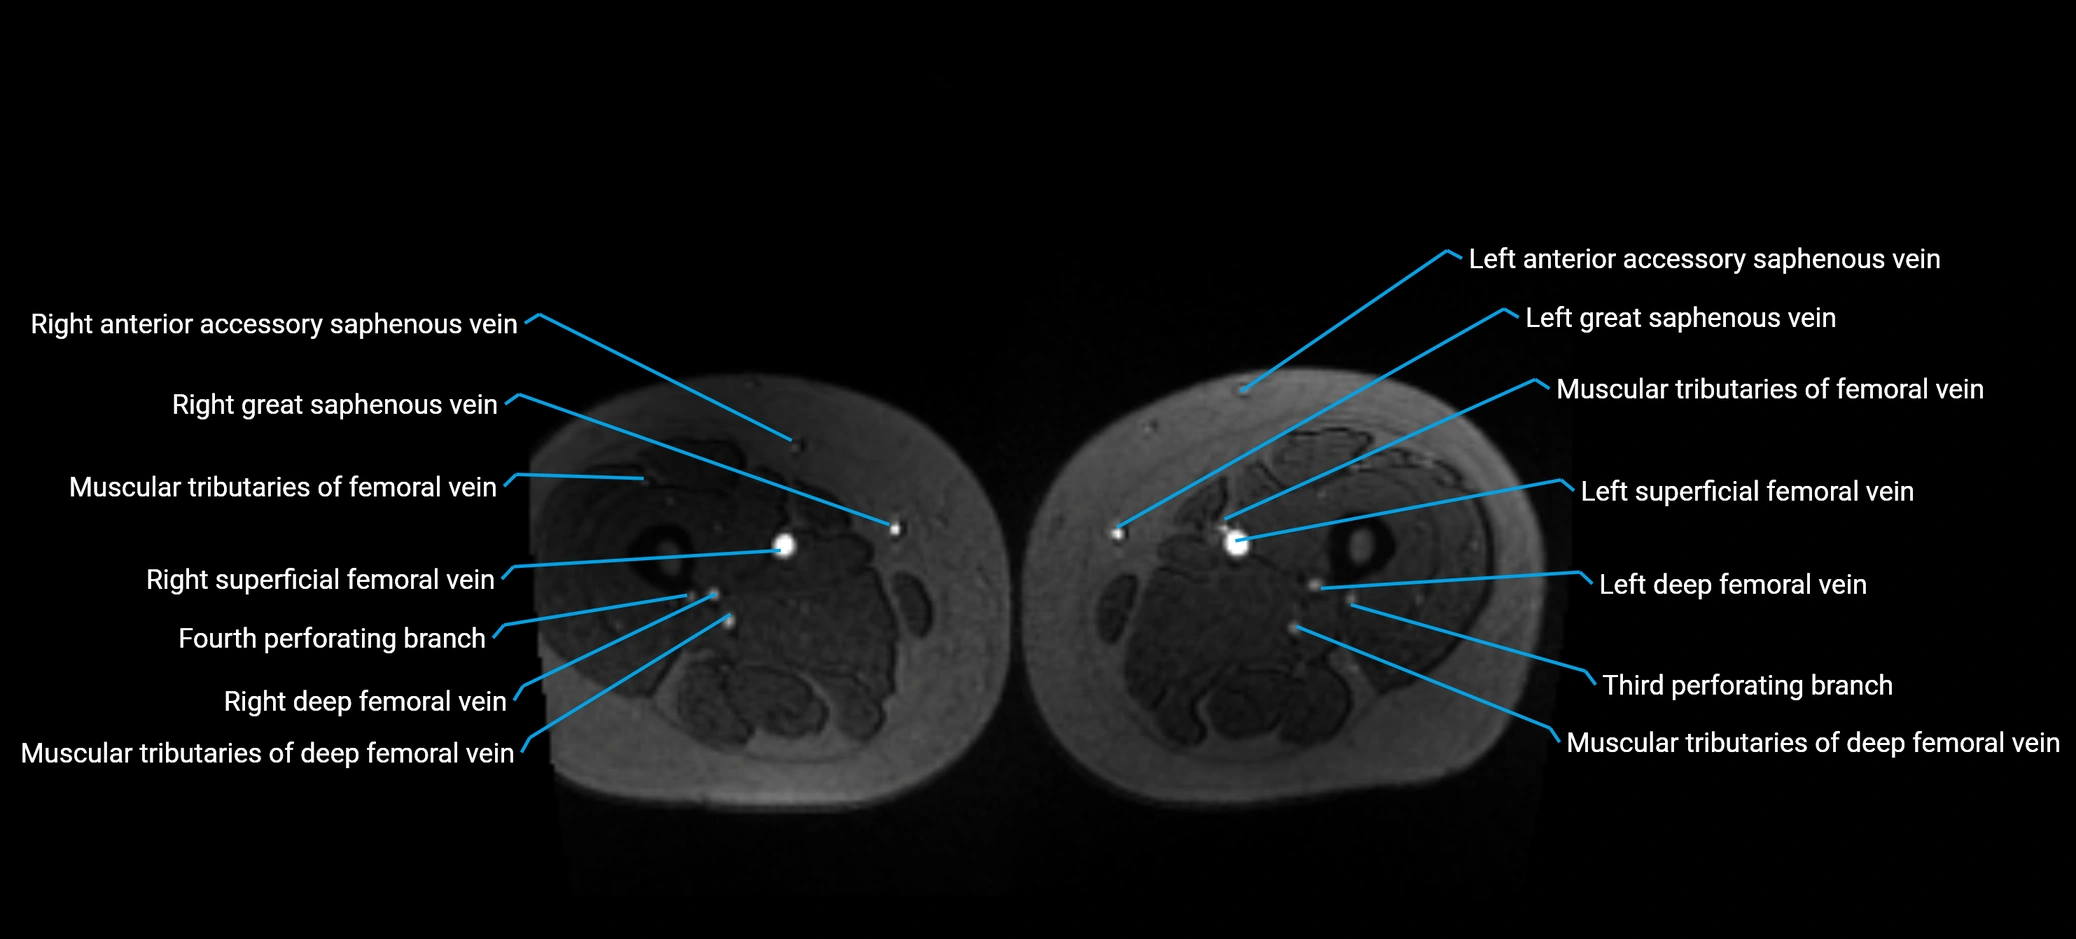

MRI image

image